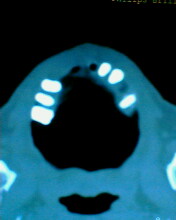

患者:男71岁,右侧上颚肿物无痛性生长7年.

右上颌骨近中线部见类圆形低密度区,上方见一液平,周围见一薄硬化环,前下方见一牙根,后方累及水平板。上方突入鼻腔前下部,下方突入口腔。

考虑:右侧上颌骨囊肿伴感染。